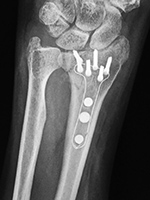

Short hip nail with helical screw and distal interlocking screw

Short hip nail with helical femoral neck screw

This stabilizes an intertrochanteric fracture.

There is also a helical femoral neck screw.

There is an oblique intertrochanteric locking screw and two distal locking screws.

This stabilizes an intertrochanteric fracture. From Taljanovic, 2005